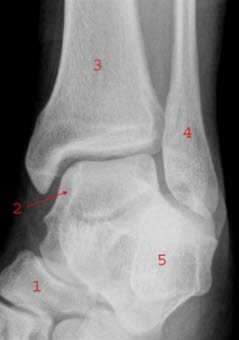

RTG - staw skokowy, projekcja skośna: 1. Kość łódkowata (os naviculare), 2. Kość skokowa (talus), 3. Kość piszczelowa (tibia), 4. Kość strzałkowa (fibula), 5. Kość piętowa (calcaneus)

Niestabilne złamanie stawu skokowego: Złamanie (1) dystalnej części kości strzałkowej z rozerwaniem więzozrostu (2), widełki kostki wyraźnie rozsunięte, kość piszczelowa (3), kość skokowa (4)